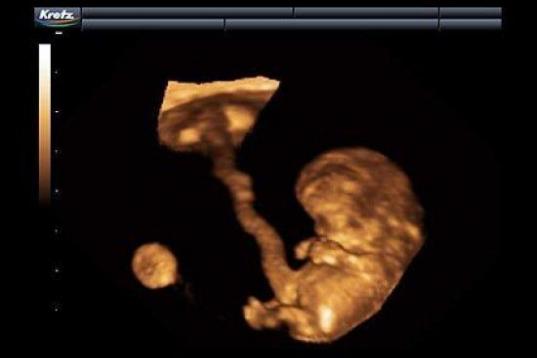

En esta galería puedes ver en fotos como es el desarrollo de un feto de semana en semana:

Desarrollo del feto, en fotos